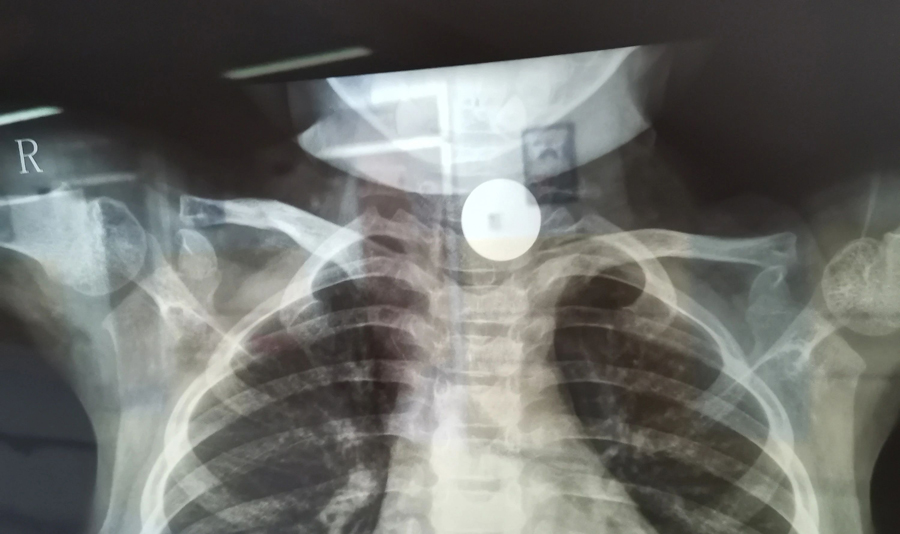

小花(化名)是4岁的小女孩,家住德惠市。小花曾说自己吞咽过一枚硬币并已排出,粗心的家长便没再关注。但此后一段时间里,小花出现进食缓慢情况且越来越重,家长这才怀疑硬币可能还在体内,所以带小花在当地医院拍了X光片,发现其食道入口处的确有异物。医生建议到上级医院手术,于是家长带孩子马不停蹄地赶到蜜桃视频 。

了解了患儿的情况后,国家儿童医学中心、首都医科大学附属北京儿童医院耳鼻喉头颈外科常驻专家、蜜桃视频 副院长张薇仔细看了患儿的X光片,明确了异物的存在和准确位置。由于异物存留时间长,食道是否有肉芽增生、有无穿孔等情况都不明确,张薇副院长决定采用全麻下通过食道镜直视下行异物取除术。